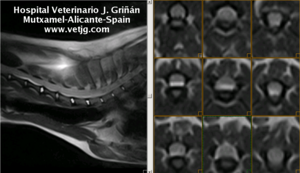

Caso 2: imágenes de resonancia magnética de un perro con síndrome cervical motivado por una hernia discal a nivel de C3-C4

Copyright 2017, Hospital Veterinario JG Mutxamel - Alicante - España